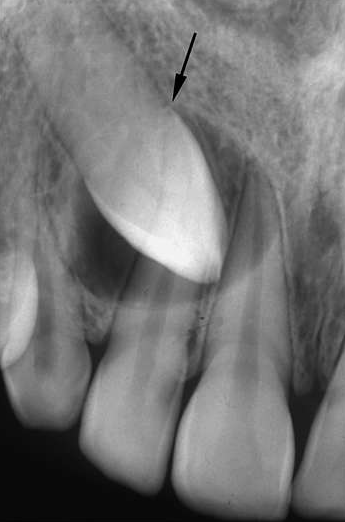

Aspectul tipic pentru o forma de mici dimensiuni este de radiotransparenta uniloculara, care inconjoara coroana unui dinte inclus sau semiinclus si care se ataseaza la coletul dintelui. In evolutie, atasarea la coletul dintelui este relativa pe imaginea radiografica.

Radiotransparenta este bine delimitata, cu contur net, adeseori discret radioopac; in cazul in care a fost suprainfectat, limitele chistului par mai putin nete. Trebuie avut in vedere faptul ca exista o serie de variatiuni ale acestui aspect radiografic.